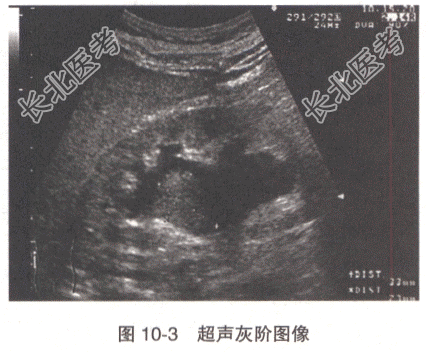

患者,女性,66岁。血尿腰痛1个月余,超声检查显示(图10-3):右肾中部低回声肿块,大小约32mm×22mm,膀胱右侧壁输尿管开口处探及一低回声,内见条状血流信号(图10-4),右侧输尿管开口处未见喷尿现象。